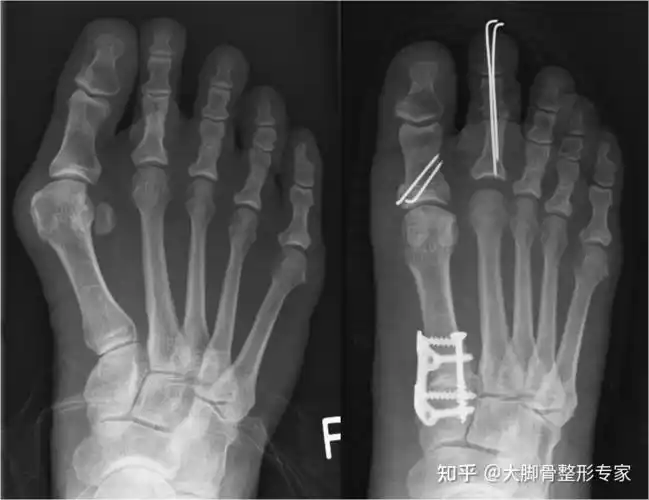

俗称"大脚骨",现行右足矫形,软组织,籽骨松解复位 chevron截骨 关节囊